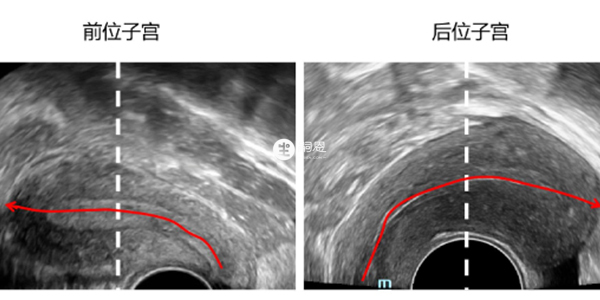

子宮前位是指子宮體走形向前指向陰道後穹隆,前位子宮更靠近肚皮。而後位子宮宮體向後走形,子宮位置更靠近臀部。而陰超檢查子宮是婦科超聲中最常用的方法,有經陰道和經腹部檢查,子宮前位和後位在這兩種B超檢查下區別如下:

1、以中線為標準(影象上虛線),縱斷面掃查超聲影象上宮腔內膜的走形靠近探頭(影象左邊)的是為前位子宮(紅色箭頭),內膜走形向影象右邊的是後位子宮(紅色箭頭)。